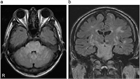

1. 高血圧性脳症は高血圧緊急症のひとつに含まれ、本来脳血管自動調節能(cerebral autoregulationを有する脳血管に閾値を超えた高血圧負荷がかかり、脳血管のvasospasmおよび血液脳関門BBBのbreak-through現象による血管原性浮腫を生じ、可逆的あるいは非可逆的な組織学的変化が起きる状態である。

1. 従来、このような病態はCTのみでは同定しにくいこともあったが、近年、MRI、MRA、脳灌流画像などにより、reversible cerebral vasoconstriction syndromeRCVSやPRESposterior reversible encephalopathy syndromeといったダイナミックな病態として捉えられるようになり、正しい診断が迅速な治療に結びつくようになってきた。